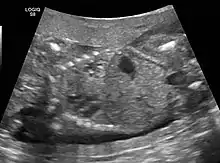

CPAMs are often identified during routine prenatal ultrasonography. Identifying characteristics on the sonogram include: an echogenic (bright) mass appearing in the chest of the fetus, displacement of the heart from its normal position, a flat or everted (pushed downward) diaphragm, or the absence of visible lung tissue.

CPAMs are classified into three different types based largely on their gross appearance. Type I has a large (>2 cm) multiloculated cysts. Type II has smaller uniform cysts. Type III is not grossly cystic, referred to as the "adenomatoid" type. Microscopically, the lesions are not true cysts, but communicate with the surrounding parenchyma. Some lesions have an abnormal connection to a blood vessel from an aorta and are referred to as "hybrid lesions."

Imaging

The earliest point at which a CPAM can be detected is by prenatal ultrasound. The classic description is of an echogenic lung mass that gradually disappears over subsequent ultrasounds. The disappearance is due to the malformation becoming filled with fluid over the course of the gestation, allowing the ultrasound waves to penetrate it more easily and rendering it invisible on sonographic imaging. When a CPAM is rapidly growing, either solid or with a dominant cyst, they have a higher incidence of developing venous outflow obstruction, cardiac failure and ultimately hydrops fetalis. If hydrops is not present, the fetus has a 95% chance of survival. When hydrops is present, risk of fetal demise is much greater without in utero surgery to correct the pathophysiology. The greatest period of growth is during the end of the second trimester, between 20–26 weeks.

A measure of mass volume divided by head circumference, termed cystic adenomatoid malformation volume ratio (CVR) has been developed to predict the risk of hydrops. The lung mass volume is determined using the formula (length × width × anteroposterior diameter ÷ 2), divided by head circumference. With a CVR greater than 1.6 being considered high risk. Fetuses with a CVR less than 1.6 and without a dominant cyst have less than a 3% risk of hydrops. After delivery, if the patient is symptomatic, resection is mandated. If the infant is asymptomatic, the need for resection is a subject of debate, though it is usually recommended. Development of recurrent infections, rhabdomyosarcoma, adenocarcinomas in situ within the lung malformation have been reported.[4]